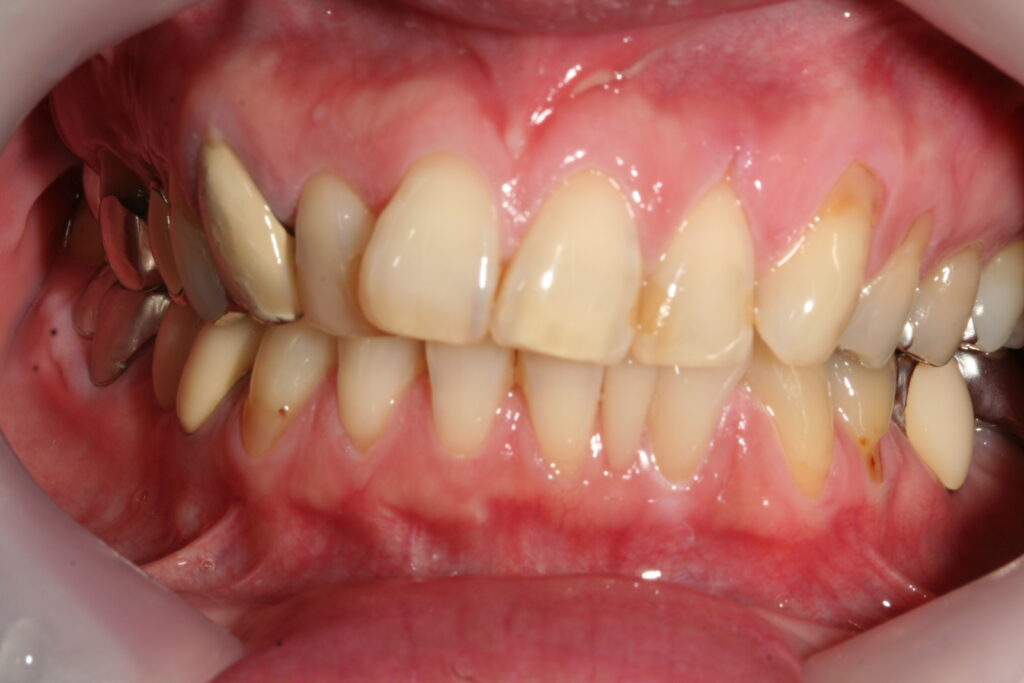

審美歯科 2018.07.24 症例紹介 45歳女性下の前歯の隙間が気になるということで来院。一本だけ治療し、ポーセレンラミネートべニアで審美治療を行いました。治療回数は2回です。 症例紹介 審美 歯科 佐賀前の記事 お盆の休診日次の記事